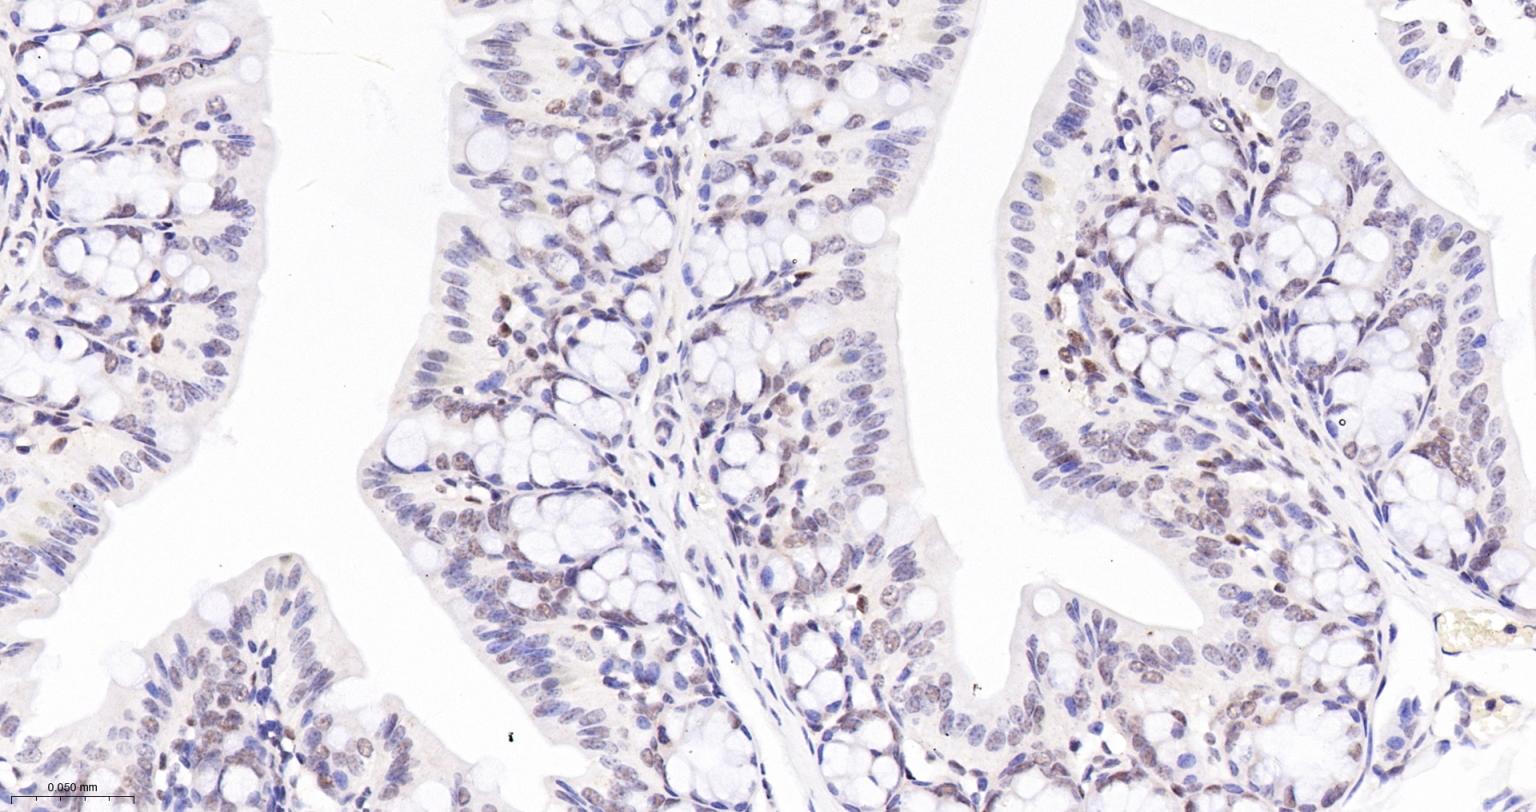

Paraformaldehyde-fixed, paraffin embedded Mouse Colon; Antigen retrieval by boiling in sodium citrate buffer (pH6.0) for 15 min; The section was incubated with CDC40 Monoclonal Antibody, Unconjugated (bsm-61342R) at 1:200 overnight at 4°C, followed by conjugation to the bs-0295G-HRP and DAB (C-0010) staining.